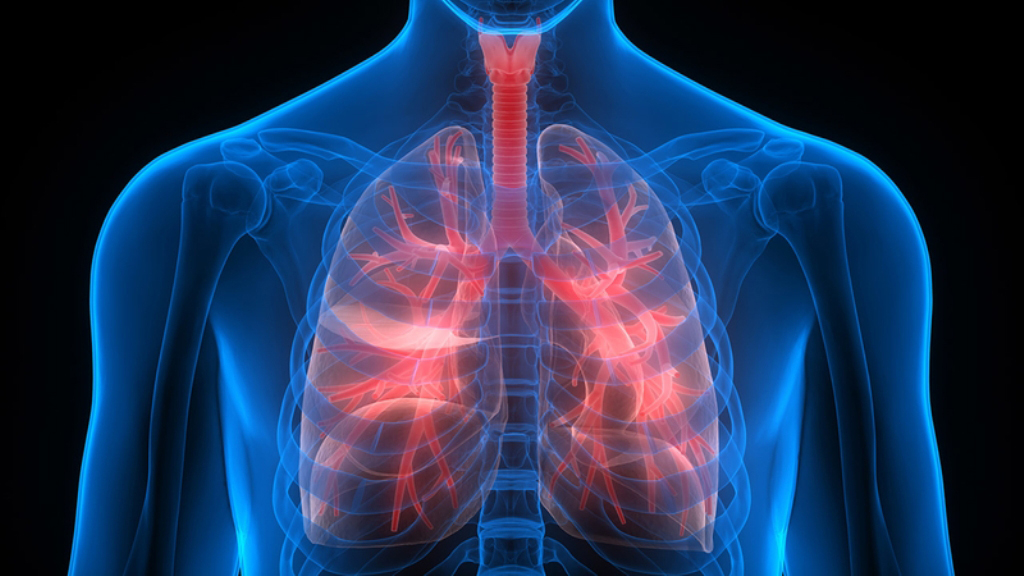

श्वासनलीको संक्रमण भनेको के हो ?

नाक, मुख, घाँटी वा फोक्सोमा हुने कुनैपनि किसिमको संक्रमणलाई श्वासप्रश्वास नलीको संक्रमण भनिन्छ। साधारणतया यस्तो संक्रमण जीवाणुको कारणले हुन्छ तर वीषाणुको कारणले पनि हुन सक्छ।

गम्भीर खालको चोट लागेमा वा टाउकोमा चोटपटक लागेको बिरामी लामो समयसम्म ओछ्यानमा पल्टिरहनु पर्ने भएमा उसको फोक्सोको चाल र गतिमा कमी आउँछ। जसले गर्दा फोक्सोभित्रबाट निस्किने खकारलाई बिरामीले खोकेर बाहिर निकाल्न सक्दैन। यसरी फोक्सोभित्र जमेको खकारले संक्रमण गराउने र संक्रमणलाई झन् खराब बनाई जटिल बनाउँछ।

घाँटी र फोक्सोमा संक्रमण हुने कारण

विषाणुबाट पनि श्वासप्रश्वास नलीमा गम्भीर संक्रमण हुनसक्छ जस्तै निमोनिया साथै नाक, मुख र घाँटीमा संक्रमित साधनहरु जस्तै रुमाल, मास्क, ओछ्यान, सिरक, आदि प्रयोग गरेमा वा प्रदुषित हावामा बिरामीले श्वासप्रश्वास लिएमा श्वासप्रश्वास नलीमा संक्रमण हुने गर्दछ।